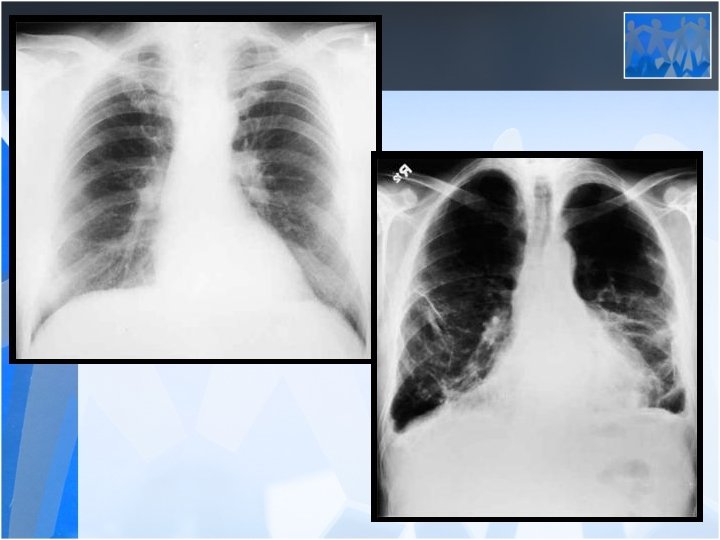

Asbestosis (Diffuse Interstitial Fibrosis) • Most patients asymptomatic 20 -30 years after first exposure • Dyspnea with exertion-progression even in the absence of further asbestos exposure. • Bibasilar, fine end-inspiratory crackles • Corpulmonale may ensue in advanced cases • PFT: Reduced lung volumes, particularly the vital capacity and total lung capacity; diminished DLCO • Cigarette smoke may accelerate the progression of pulmonary fibrosis after asbestos exposure

• The most common clinical presentations are dyspnea, chest pain, unilateral decreased volume of the affected hemithorax (frozen chest) • Nodular thickening of the pleura, irregular thickening of the interlobar fissure, absence of mediastinal shift with massive pleural effusion (frozen chest) • Diagnosis by histologic examination • Treatment oncologic and surgical if possible, prognosis is poor